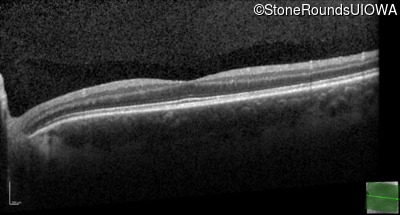

Age at visit: 17 years

OD OS

This 17 year old male had normal vision until about 6 months earlier when he began to lose central vision. The left eye may have been affected prior to the right eye.